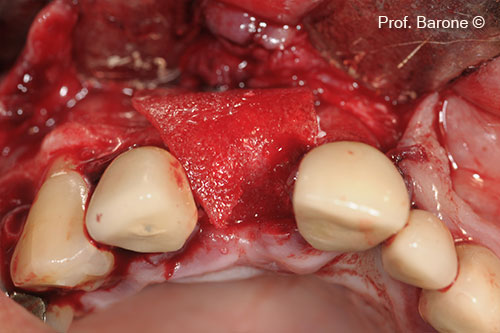

Augmented Ridge

Implant site preparation

Implant inserted in the augmented ridge